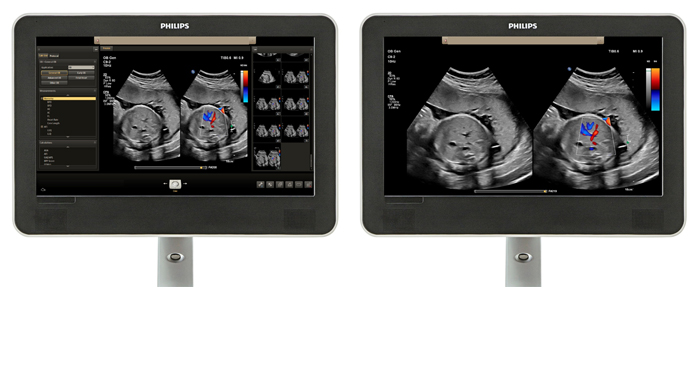

At the touch of a button, the new MaxVue high-definition display brings extraordinary visualisation of anatomy with 1,179,648 additional image pixels compared to a standard 4:3 display format mode. MaxVue enhances ultrasound viewing during interventional procedures and provides 38% more viewing area to optimise the display of dual, side/side, biplane, and scrolling imaging modes.

MaxVue offers a 38% greater viewing area.

MaxVue offers high definition display at the touch of a button.

MaxVue offers 1,179,648 additional image pixels compared to a standard 4:3 display format mode.